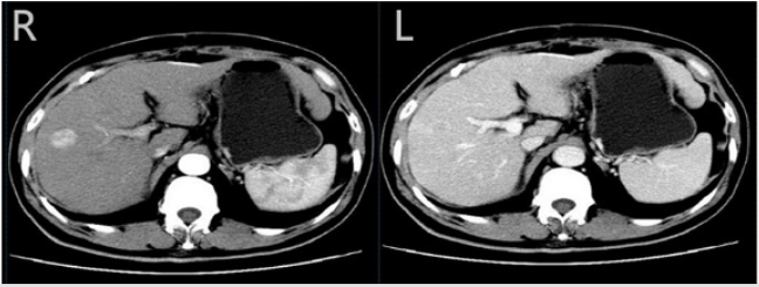

Figure 1: Computed tomography (CT) scan of the liver Computed tomography (CT) scan of the liver showed a 2 cm tumour in the right lobe with arterial phase hyperenhancement (R) and venous phase washout (L)

A Computed tomography (CT) scan of the liver showed 2 cm tumors in the right lobe with arterial phase hyperenhancement and venous phase washout and background liver appeared cirrhotic. This diagnosis was confirmed by pathology, cirrhosis and hepatocellular carcinoma, caused possibly by nonalcoholic steatohepatitis. The woman was managed with surgical method and transcatheter arterial chemoembolization (TACE) at our institution (Figure 2).